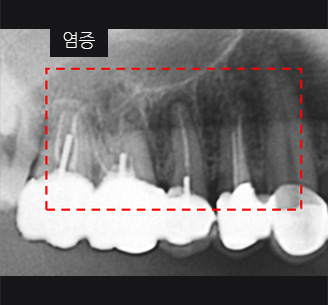

치근단 염증

신경관 소독

신경관 약재삽입

약재주입 후 반응